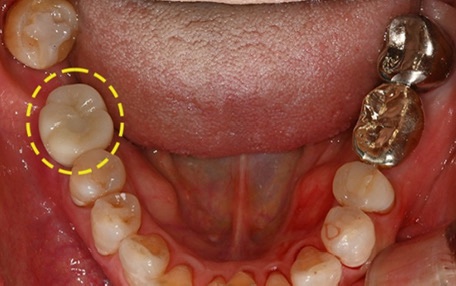

치료는 어떻게 진행될까요?

처음 내원하시면

파노라마 엑스레이와 필요 시 3D CT 촬영을 통해

상악동 위치, 뼈의 높이와 두께, 신경 위치까지

전체적으로 확인합니다.

이 진단을 바탕으로

임플란트를 바로 진행할 수 있는지,

상악동 거상술과 함께 진행하는 것이 좋은지

개인 상태에 맞춰 치료 계획을 세웁니다.

상황에 따라

임플란트와 상악동 거상술을

같은 날 함께 진행하기도 하고,

뼈가 충분히 자리 잡은 뒤

단계적으로 이어가는 경우도 있습니다.

중요한 점은 무리하지 않고,

각 단계가 자연스럽게 이어지도록

치료 흐름을 설계하는 것입니다.